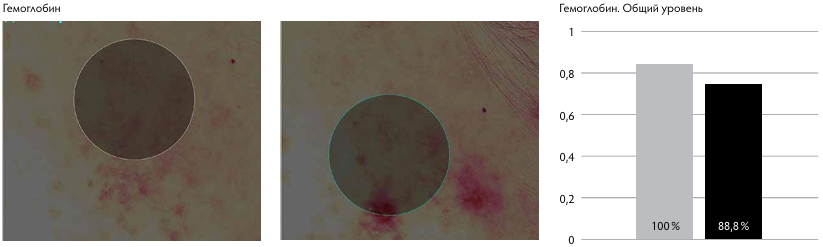

Рис. 1. Показатели пациентов I группы.

Рис. 1. Показатели пациентов II группы.

По данным Miravex Antera, в I группе отмечалось уменьшение содержания гемоглобина в среднем на 52–65 %, что говорит о снижении насыщения кожи поверхностными сосудами. Это свидетельствует в пользу эффективности методики при лечении пациентов с постакне, гиперпиг ментацией, поствоспалительными пятнами.

У пациентов II группы, по данным Miravex Antera, уменьшение содержания гемоглобина отмечалась в среднем на 15–21 %, меланина — на 1–5 %, улучшение текстуры кожи — на 18–25 %, снижение глубины морщин на 15–27 %, что сопоставимо с результатами пациентов I группы. По данным GAIS, у пациентов I группы отмечается удовлетворённость результатами процедуры на три балла, со стороны врача — тоже на три балла. У пациентов II группы пациенты расценивают результат на 2,4 балла, врач — на 2,4 балла.